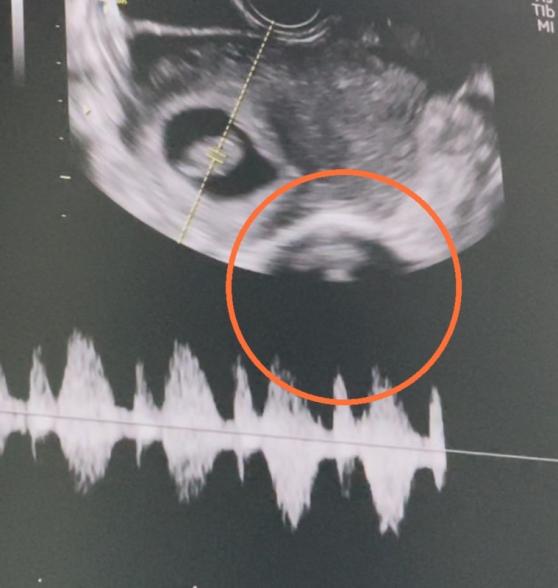

妊娠8w3dのエコーです。

左上に映っている子の心臓を 確認すると「心臓動いてますね。元気です」と言われ即診察が終わりました。

最近その診察の際に撮っていた動画を見直すと、もう一人映っているように感じました。

このオレンジの丸の中は赤ちゃんでしょうか?それとも臓器などでしょうか?

赤ちゃんだった場合、 位置などは問題ないでしょうか?

二卵性双生児でしょうか?

拝見させていただきましたが、子宮内にいるのはお一人だと思いますよ。

双子ちゃんであれば、同じ子宮内に袋の中に入っていると思います。子宮のすぐ隣の臓器に当たるのかな?と思いました。

また先生にもご確認をお願いします。